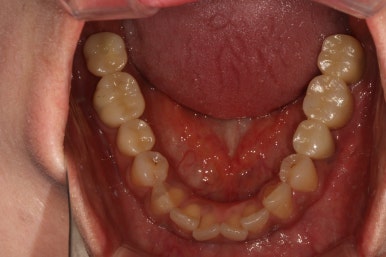

아래턱 교합면입니다.

역시나 충치가 심했던 사랑니는 제거되었고, 비어있던 자리는 임플란트로 대체되었습니다.

색깔과 모양이 상당히 마음에 드는 완성도입니다.

이제 진짜.. 자연치라고 해도 잘 모를 정도로 치과치료의 완성도가 높아졌습니다.